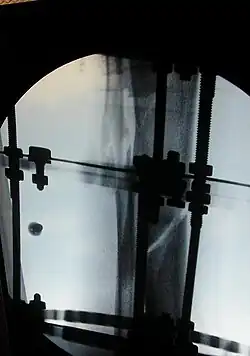

The photographs and radiographs illustrate the application and emplacement of an external fixator, an Ilizarov apparatus, to repair the open fracture of the lower left leg of a man. The photographs were taken four weeks after the patient fractured the shinbone (tibia) and the calfbone (fibula) of his left leg, and two weeks after the surgical emplacement of the Ilizarov apparatus to immobilise the leg and isolate the wound and fracture site to facilitate healing.

X-ray of the open fracture of the left leg; the external fixator was installed ca. 24 hrs. in hospital. -

X-ray of the open fracture site immediately after installation of the Ilizarov apparatus. -